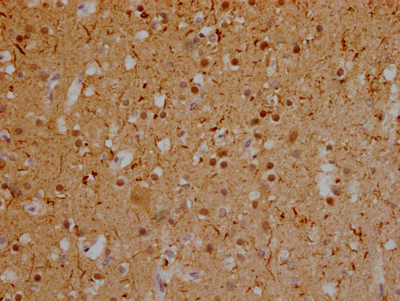

• IHC image of CSB-RA246354A0HU diluted at 1:100 and staining in paraffin-embedded human glioma cancer performed on a Leica BondTM system. After dewaxing and hydration, antigen retrieval was mediated by high pressure in a citrate buffer (pH 6.0). Section was blocked with 10% normal goat serum 30min at RT. Then primary antibody (1% BSA) was incubated at 4℃ overnight. The primary is detected by a Goat anti-rabbit IgG polymer labeled by HRP and visualized using 0.05% DAB.

• IHC image of CSB-RA246354A0HU diluted at 1:100 and staining in paraffin-embedded human brain tissue performed on a Leica BondTM system. After dewaxing and hydration, antigen retrieval was mediated by high pressure in a citrate buffer (pH 6.0). Section was blocked with 10% normal goat serum 30min at RT. Then primary antibody (1% BSA) was incubated at 4℃ overnight. The primary is detected by a Goat anti-rabbit IgG polymer labeled by HRP and visualized using 0.05% DAB.